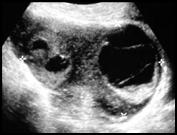

Right adnexal pain, no fever or wbc

Ruptured Hemorrhagic Cyst